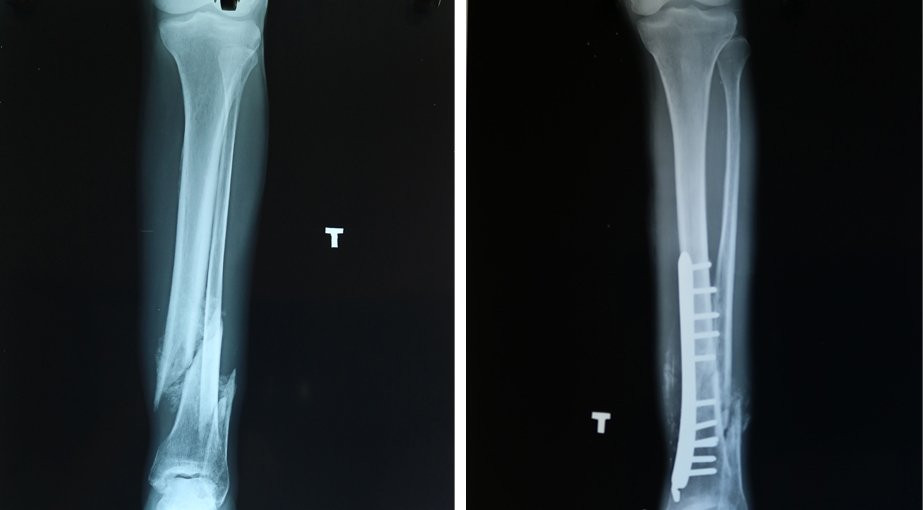

Kết quả thăm khám, bác sĩ chẩn đoán bệnh nhân bị gãy 1/3 dưới xương 2 cẳng chân trái, cal lệch. Bệnh nhân được chỉ định phẫu thuật chỉnh xương.